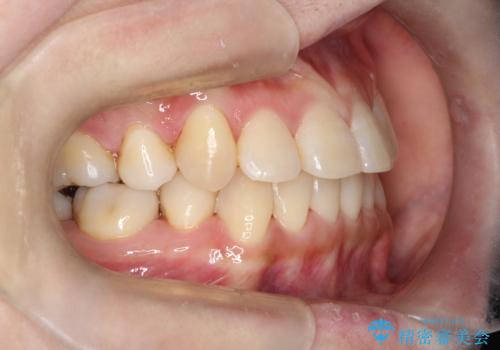

コンプレックスだった前歯のガタガタがここまで綺麗になるなんて!!

治療に関して期間こそかかってしまったものの、見た目、嚙み合わせ及び、治療期間や施術内容に大変ご満足いただきました。